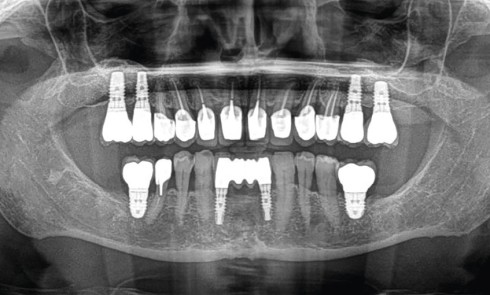

Article réservé à nos abonnés Préalables cliniques à la pose d’implant

L’implantologie fait actuellement partie des options de traitement prédictibles permettant de remplacer les dents manquantes, avec des taux de survie...

Article réservé à nos abonnés Analyse préopératoire en implantologie : pourquoi et comment établir un projet prothétique ?

Le projet implantaire s’inscrit dans le plan de traitement global, qui comprend lui-même deux grandes phases de traitement : une phase...